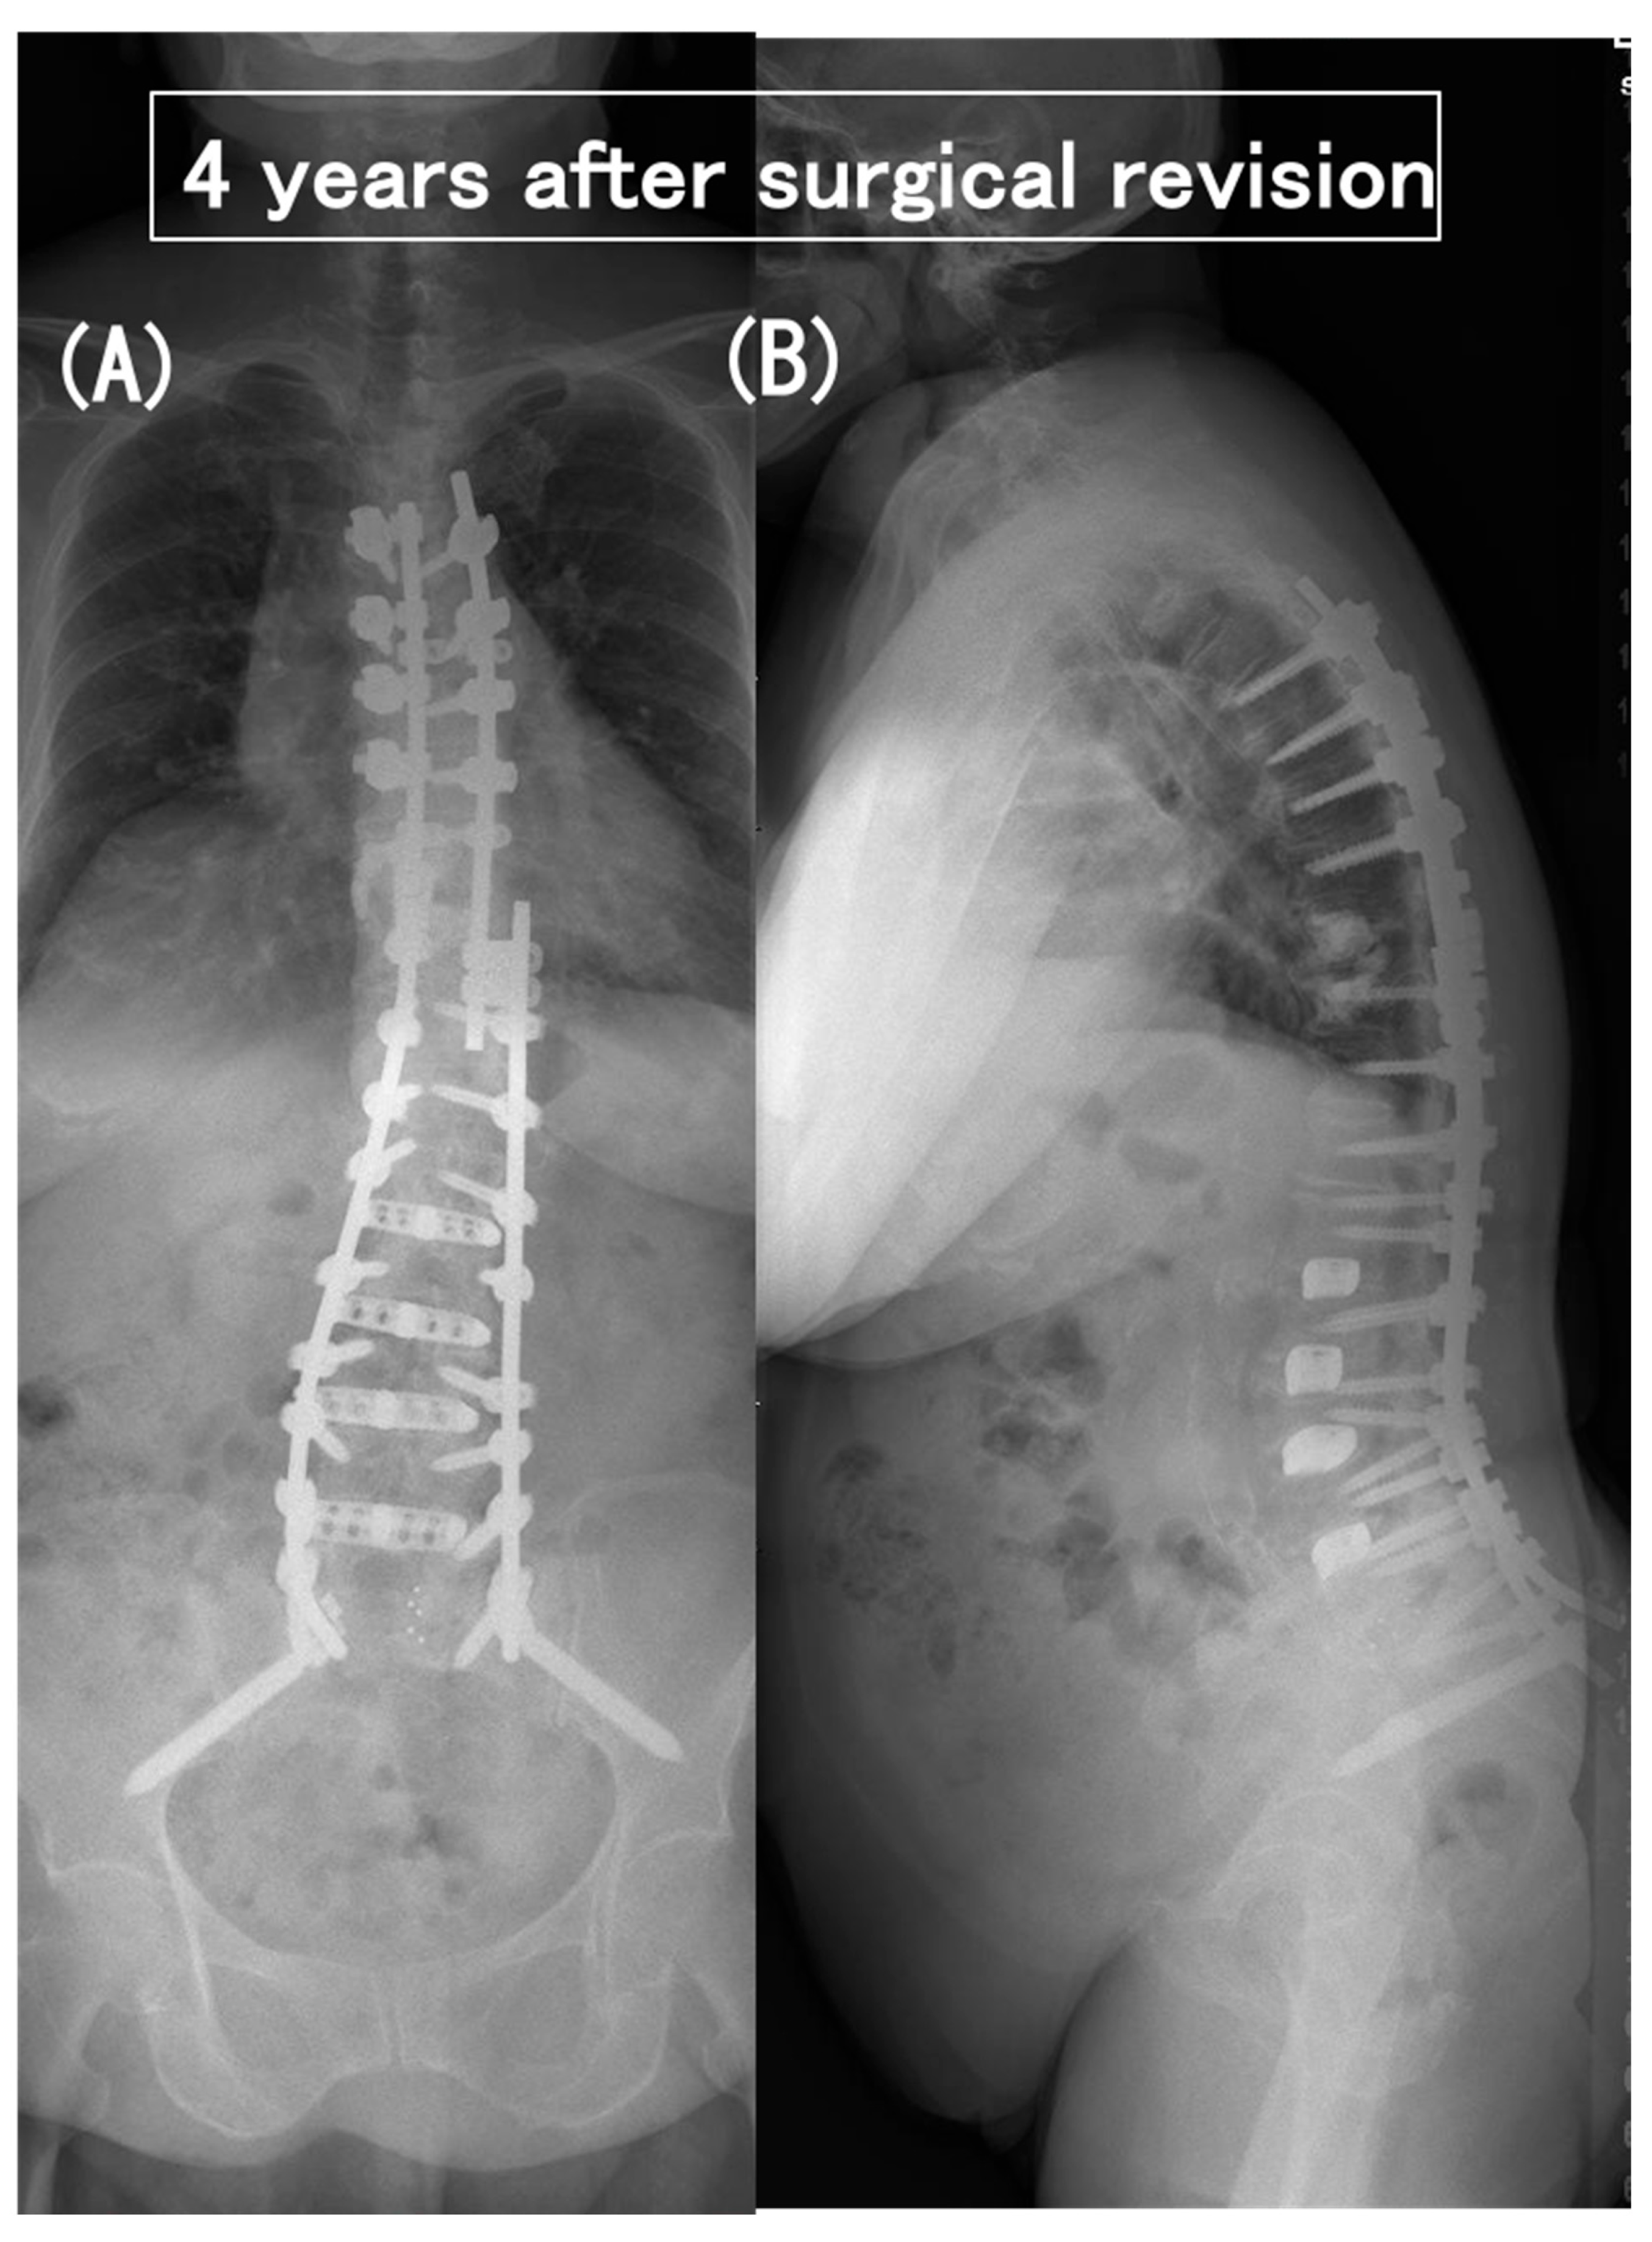

3.6. Case Presentation

- Case no. 6

- 2.

- Case no. 4

| Case No. | Modified Frankel Grade § | Vertebral Collapse | Segmental Instability | Time Interval Between the Initial Op and PJF (month) | Proximal Extension of Fusion | Decompression | Modified Frankel Grade | FU (months) | |||||||||

| 1 | D3 | T8, T10 | – | 13 | T5 | − | D3 | 79 | |||||||||

| 2 | D1 | T10 | UIV–UIV + 1 | 20 | T5 | - | D3 | 37 | |||||||||

| 3 | C | T9, T10 | UIV–UIV + 1 | 4 | T3 | + | D2 | 77 | |||||||||

| 4 | D1 | T10 | UIV–UIV + 1 | 6 | T5 | + | D2 | 40 | |||||||||

| 5 | C | T9 | UIV–UIV + 1 | 14 | T5 | + | D3 | 74 | |||||||||

| 6 | C | – | UIV–UIV + 1 | 2 | T5 | + | D2 | 96 | |||||||||